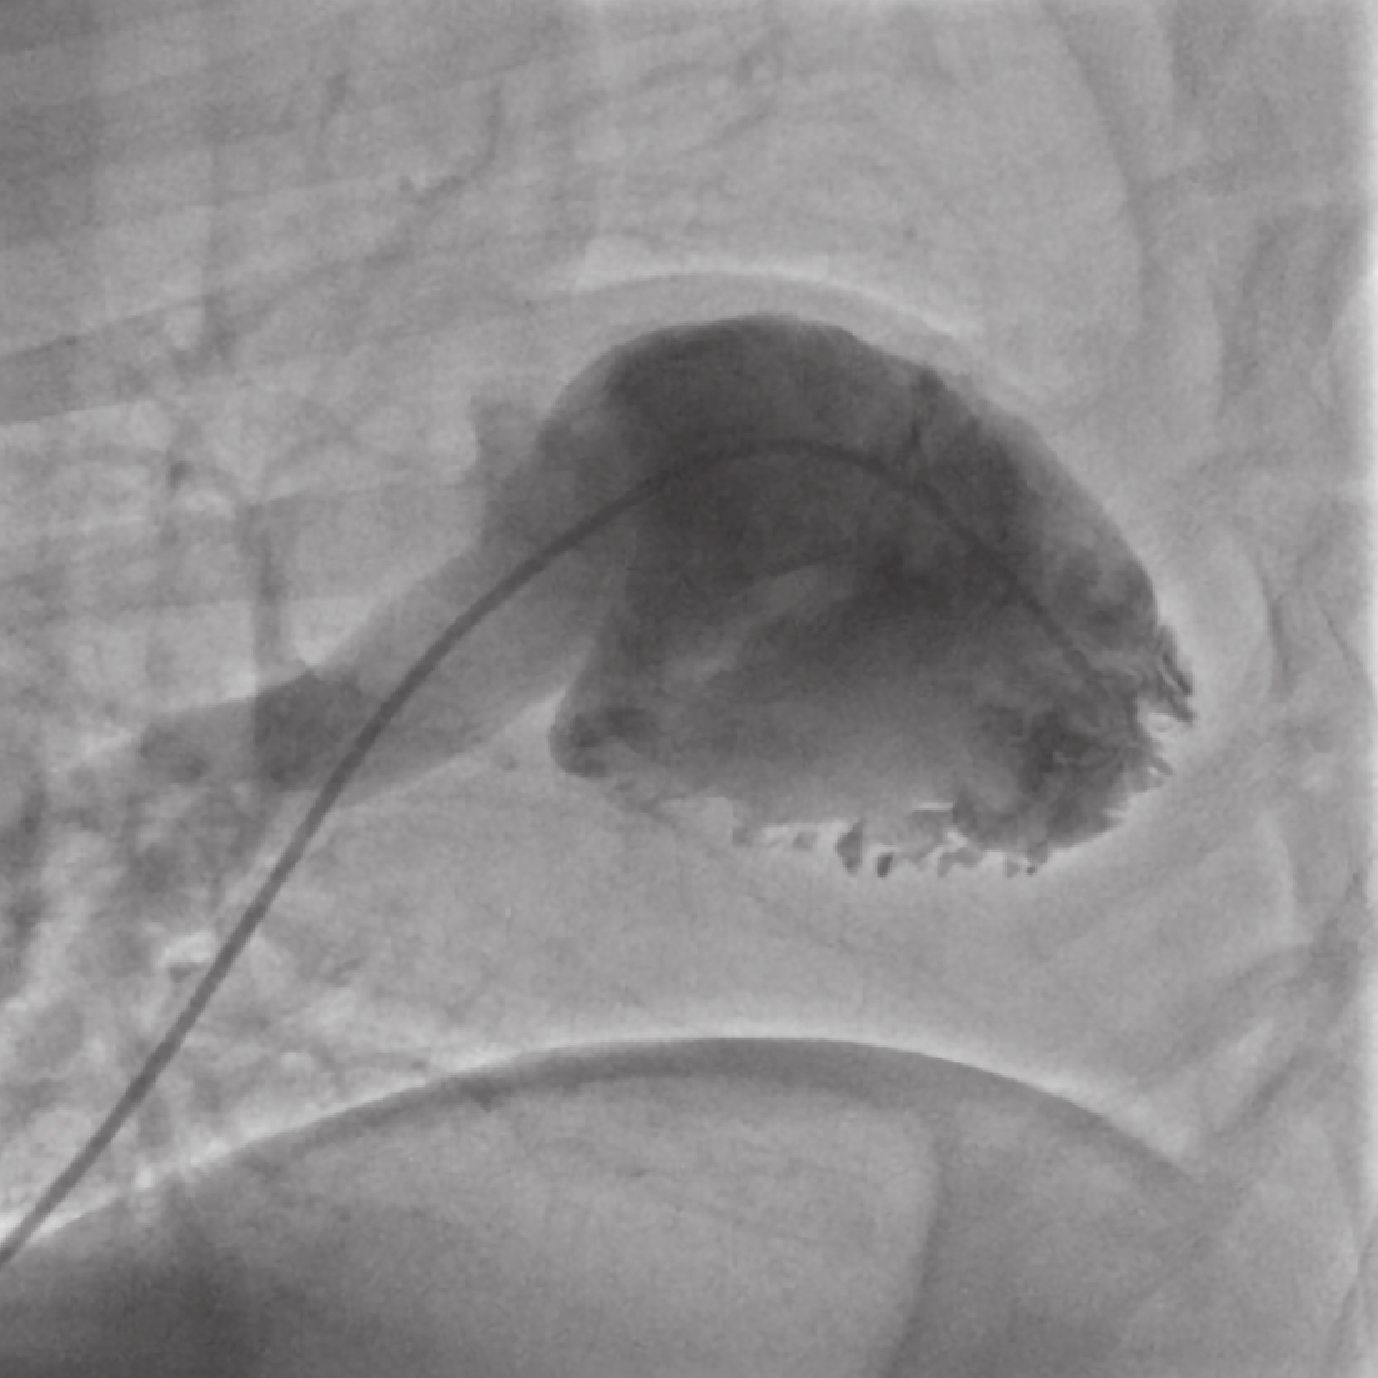

山羊左側臥位(圖 1),常規麻醉和機械通氣后,放置經食管超聲,常規消毒鋪單,沿左側股靜脈將豬尾巴導管送至右心室(圖 2);右側前外側第 4 肋間進入胸腔,懸吊心包,顯露右心房,全身肝素化(肝素 1.5 mg/kg)后,用 4-0 Prolene 線帶氈片縫雙荷包。尖刀片從荷包中心做右心房小切口,送入自制的腱索切割器(圖 3),收緊荷包線止血,造影明確三尖瓣環位置,超聲確認切割器進入三尖瓣平面;在超聲引導下,切割器尖端回拉住三尖瓣前瓣葉腱索,推送手柄使頭部尖端閉合切斷腱索,再次觀察超聲反流情況,如果沒有觀察到明顯反流,重復過程直至出現中至重度反流后,撤離切割器,結扎荷包線,止血關胸,魚精蛋白按照 1∶1 的比例中和肝素。

所有山羊 TR 模型成功建立(圖 4、圖 5);在術后及隨訪沒有山羊死亡,所有山羊術前超聲及造影提示無任何反流,在手術期間均出現短暫的房室早搏,心率由術前(83.7±8.3)次/min 上升至(146.0±35.6)次/min;術后即刻右心房壓力從 5.1 mm Hg 升高至 9.2 mm Hg(P<0.05),三尖瓣跨瓣壓差(P=0.281)、流速(P=0.129)及直徑(P=0.175)無明顯改變,TRA/RAA 均在 40% 以上提示重度反流的成功建立;見表 1。術后隨訪 3 個月,無山羊死亡,2 例出現輕度腹部膨隆,山羊跨瓣壓差(P=0.224)及流速(P=0.204)均值與術前基線比增大,但差異均無統計學意義,TRA/RAA 較術后即刻增大(P=0.003),提示 TR 程度持續性增加;三尖瓣瓣環直徑由(2.15±0.23)cm 增加至(2.65±0.20)cm (P=0.002),實驗室檢查如肌酐、膽紅素、BNP 等與術前無明顯改變;整個隨訪期間左心功能及肺動脈壓力無明顯改變,解剖發現 5 例前瓣葉腱索損傷,1 例前后瓣葉腱索均損傷。